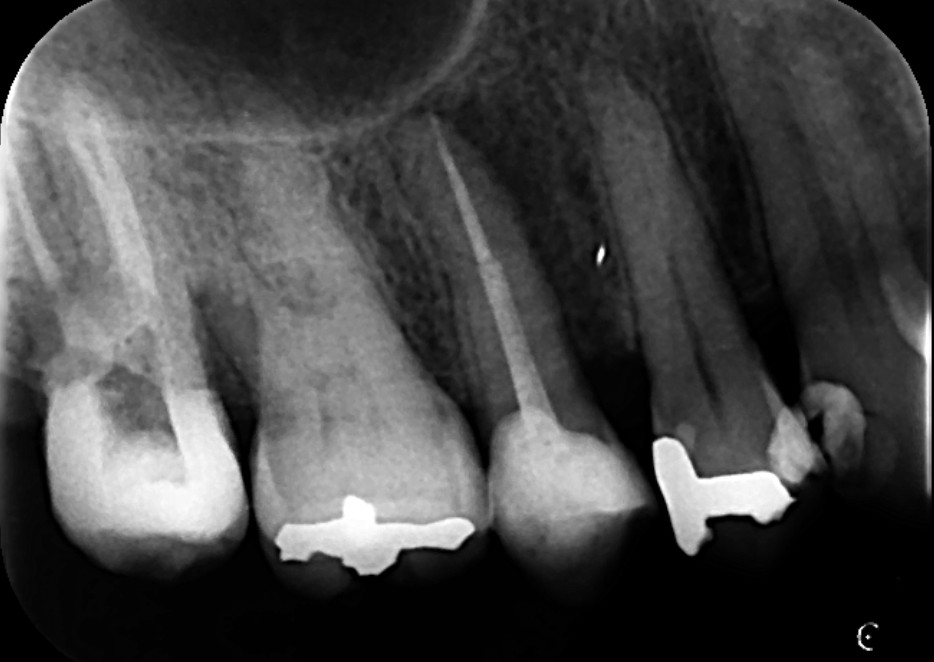

上の画像は、根管治療後のレントゲン画像です。